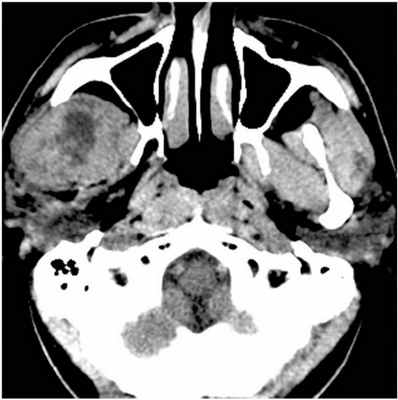

45-летний пациент обратился за помощью в отделение челюстно-лицевой хирургии с жалобами на отек в правой височной области. Припухлость не провоцировала болевых ощущений и развивалась на протяжении месяца, увеличиваясь в размерах. Признаков инфицирования в области поражения отмечено не было. В 2012 году пациент уже обращался с аналогичной проблемой в частную стоматологическую клинику. На ортопантомограмме и КТ-срезах было идентифицировано мультикистозное поражение. После биопсии стало понятно, что проблемная опухоль является амелобластомой. Пациенту была проведена процедура гемимандибулектомии. Прямо во время операции была проведена рентгенография хирургического образца опухоли для анализа состояния тканей на расстояние 1,5 см от визуализированного клинически края опухоли. Гистологический анализ подтвердил диагноз амелобластомы с атипичными признаками и мультиклеточной структурой. В 2016 году у пациента опять была отмечено припухлость в правой височной области. На МРТ было идентифицировано неоднородное усиление сигнала в данному участке размером 4,4 см × 3,7 см × 4,6 см с наличием крошечных кистозных включений (фото 4). Через доступ по скуловой кости было проведено удаление опухоли с определенным объемом окружающих тканей (фото 5-6). Сформировавшийся дефект восстановили посредством височной мышцы. После гисотоанализа хирургического образца тканей был подтверждён диагноз амелобластомы с неинвазивными краями. В данное время пациент находиться на этапе мониторинга.

Фото 4: КТ-срез, сделанный до проведения операции: визуализация рецидивирующей амелобластомы в подвисочной ямке.